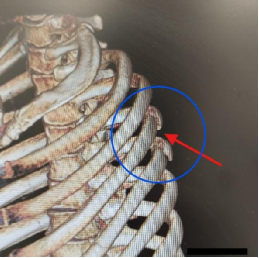

患者需手术的肋骨骨折断点位于肩胛骨深面,且患者肩胛骨已有骨折(见图三、图四)。如果进行传统的肋骨骨折内固定手术,需要切开肩胛骨周围大量肌肉层次,手术带来的创伤较大;

更为关键的是传统的肋骨骨折内固定手术需要使用医疗器械“掀开”肩胛骨才能显露手术区域,患者肩胛骨已经存在骨折(目前肩胛骨的骨折是不需要手术的),手术过程中有可能加重肩胛骨的骨折,最终可能导致肩胛骨的骨折也需要去做内固定手术。

图三 图四